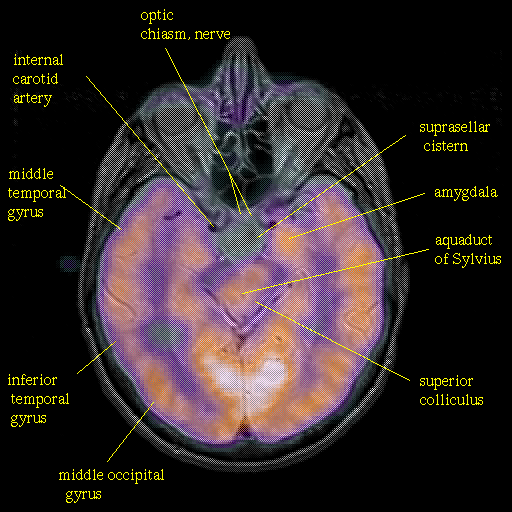

overlay : Slice 23

Slice 23